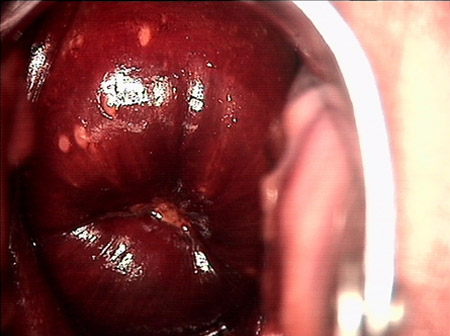

婦科leep手術(shù) 宮頸息肉

宮頸息肉

宮頸息肉 leep術(shù)后

宮頸息肉 leep術(shù)一周后

宮頸息肉 leep術(shù)兩周后

宮頸息肉 leep術(shù)三周后

宮頸息肉 leep術(shù)50天后